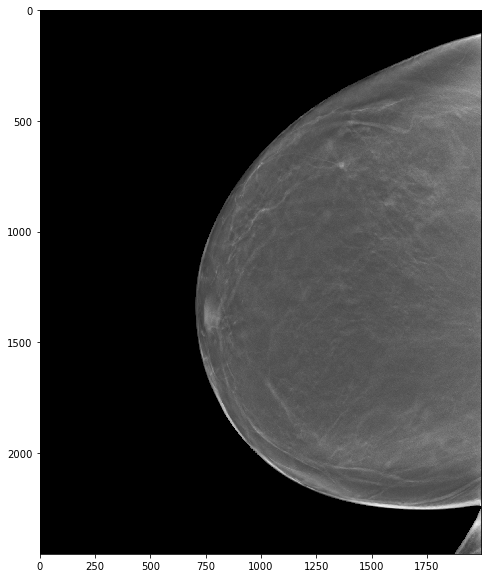

The Oregon-Massachusetts Mammography Database

OMAMA-DB

World's Largest Mammography Dataset

publicly available!

with labels!

we started with ~1 million images!

2000 x 2000 pixels